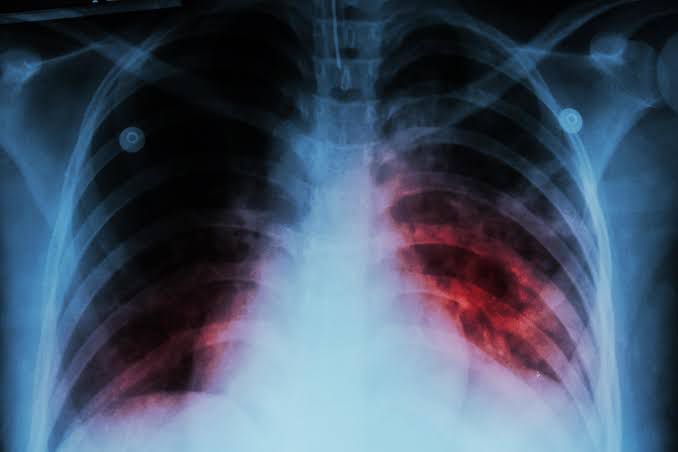

Tuberculosis (TB) is a serious illness that mainly affects the lungs. The germs that cause tuberculosis are a type of bacteria. Tuberculosis can spread when a person with the illness coughs, sneezes or sings. This can put tiny droplets with the germs into the air. Another person can then breathe in the droplets, and the germs enter the lungs